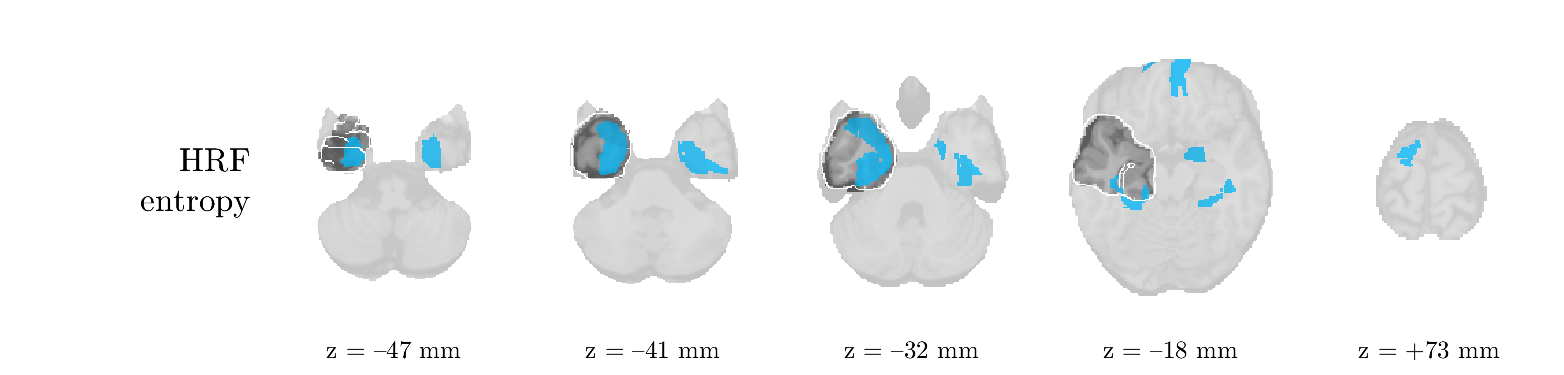

We analyze the solution with sources. Figure 1 shows the EEG signatures and HRF waveforms. One of the sources is highly correlated to the MWF reference (in grey), which was already known from Table B.3. This IED-related source had a typical low-frequency spectrum, which is expected for the typical spike-and-wave interictal discharges. The topography is relatively diffuse, although the highest amplitudes are mostly in the left hemisphere. This is in accordance with the lateralization of ictal onset zone (left temporal lobe, cfr. Table 1). There are some noteworthy observations to be made about some of the other components. The fourth has an unusually sharp spectrum, is mainly localized on two nonadjacent center electrodes, and is sustained for a single period of many seconds Hence, this component likely captured an artifact (of yet unknown origin), although we spotted no large-amplitude changes in the EEG itself. Similarly, the third source is only present at one frontal electrode, and exists in a frequency range above 20 Hz. It might represent a muscle artifact, e.g., due to frowning or twitching of some muscles in the forehead. The HRFs of all ROIs are shown in Figure 1(b). Two of the basis functions seem to have converged to a very similar waveform, which is an unfortunate possibility if two initial HRFs are too close to the same local optimum in their respective parameters. This reduces the expressive power of the basis set, which is clearly visible, since many ROIs have a nearly identical HRF. One of the twenty ROIs with the highest-entropy HRF overlapped the IOZ, although clearly this HRF (bold line) is not among the most dissimilar waveforms for this patient. This is also visible in Figure 2: both the HRF entropy and extremity maps show a small overlap with the delineated IOZ. Despite the good correspondence in the EEG domain, no significant (de)activation of the IED-component is found inside the IOZ.

We analyze the solution with sources, and show the results in Figure 3 and 4. As for patient 1, we found a source which is strongly correlated to the MWF envelope, and which had a mostly low-frequency behavior characteristic for spikes. The topography is mostly uninformative, and does not clearly correspond to the patient’s clinical data. The third source is mostly present at both sides of the head, is very sparsely active in time, and has a high-frequency content: this is most likely an artifact due to the neck muscles. Again, there is one of the highest-entropy HRFs which belongs to a ROI in the IOZ. Now, the waveform is clearly resolved from the other HRFs, through the strong initial dip (before 0 seconds). Such a dip is sometimes observed in HRFs, but its underlying physiological mechanism is not yet fully understood. It is possible that this dip reflects altered vascular autoregulation near the IOZ (cfr. the explanation in the Section 1 of the main text), or a rapid depletion in oxygen due to IED generation (before the IED becomes visible on the EEG). Figure 4 furthermore shows that the IED-related component is significantly active in parts of the IOZ, and deactive in others. As mentioned earlier, this deactivation may or may not be due to errors in sign correction. Interestingly, the ROI with the high alteration in neurovascular coupling is distinct from both the activated and deactivated ROIs.